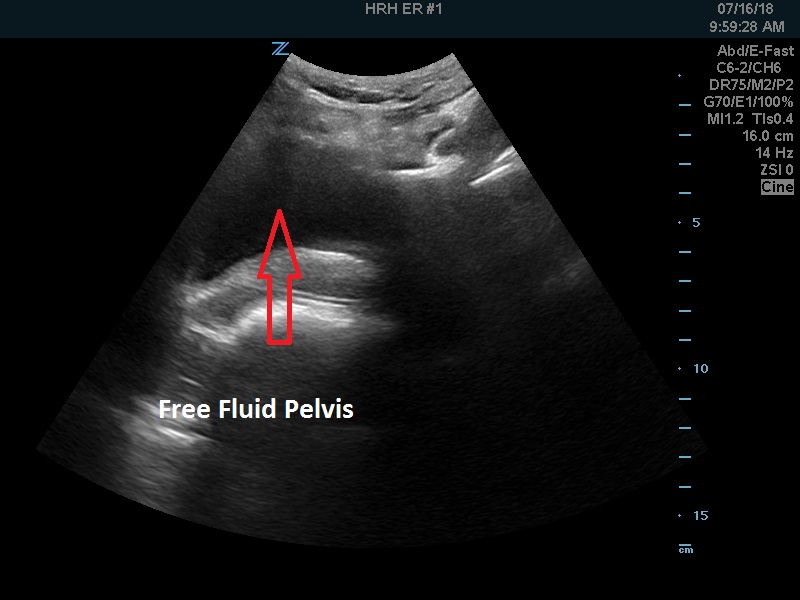

Free fluid more pronounced in the pelvis. The uterus was empty (not shown).